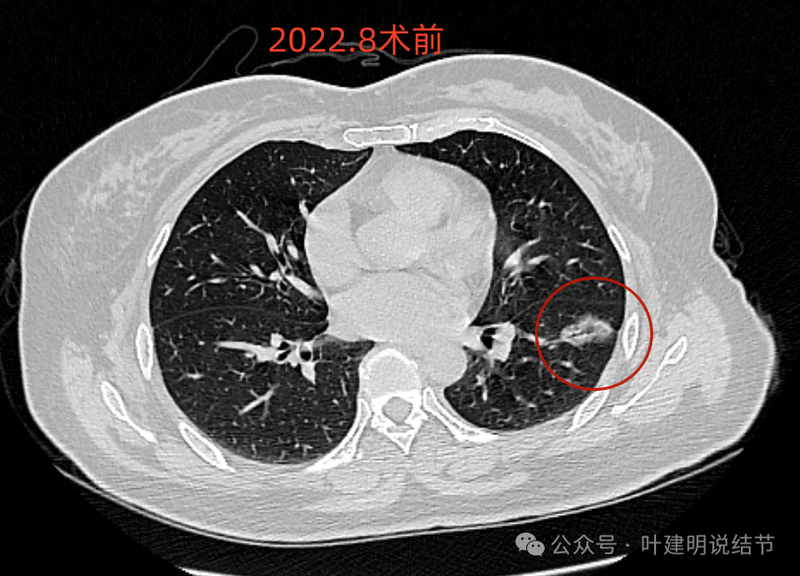

2022年8月术前左下病灶的样子,是混合磨玻璃密度,边缘毛糙,灶内有细支气管扩张,近侧有支气管截断似的,胸膜有牵拉,整体轮廓清,瘤肺边界也较清,是典型浸润性腺癌的影像表现。

基因检测结果示存在EGFR突变。